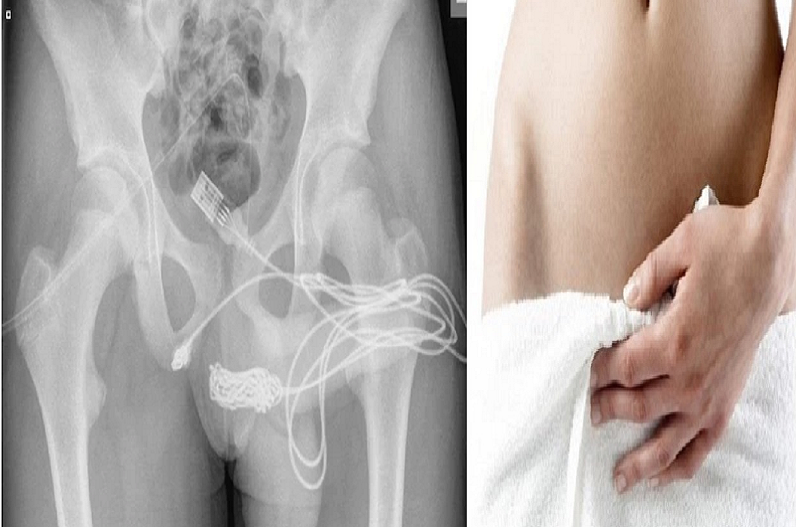

दरअसल, बच्चे को उसकी मां गंभीर हालत में अस्पताल लेकर आई थी। उसके प्राइवेट पार्ट से लगातार खून आ रहा था। जब वो टॉयलेट करता, तब उसकी स्थिति और दर्दनाक हो जाती थी। डॉक्टर्स ने उसे एडमिट कर उसका एक्सरे करवाया। इसमें उन्होंने पाया कि उसके पेट के अंदर एक यूएसबी वायर है। जब डॉक्टर्स ने उससे पूछा कि ये तार उसकी बॉडी के अंदर कैसे गया, तो उसने इसके पीछे का राज खोला। अपनी मां को कमरे से बाहर करने के बाद उसने बताया कि वो सिर्फ अपने प्राइवेट पार्ट की लंबाई अंदर से नापना चाहता था। इसके लिए वो तार को अंदर घुसा रहा था। लेकिन ऐसा करने के दौरान अचानक उससे तार का सिरा छूट गया और वो अंदर घुस गया।

लड़के ने तार को खींचकर बाहर निकालने की काफी कोशिश की। लेकिन उसकी कोशिश हर बार नाकामयाब हो जा रही थी। दरअसल, इस तार में अंदर की तरफ कई गांठें पड़ गई थी। इस वजह से खींचने पर उसे सिर्फ दर्द हो ही उसकी बॉडी मैंने अंदर से ब्लीडिंग थी, जो पेशाब के रास्ते बाहर आ रही थी। डॉक्टर्स ने तुरंत लड़के का ऑपरेशन किया और तार को बॉडी से बाहर निकाला। इसके बाद लड़के को कुछ दिन के बाद डिस्चार्ज कर दिया गया। यूरोलॉजी एक्सपर्ट्स के मुताबिक़, ऐसे सेक्सयुअल एक्सपेरिमेंट बिलकुल नहीं करने चाहिए। ये लोग टर्म के लिए भी काफी खतरनाक हो सकते हैं।

उसके प्राइवेट पार्ट से यूएसबी केबल निकला जो उसने ही अपने बॉडी के अंदर डाला था। इस घटना को यूरोलॉजी केस हिस्ट्री में सब्मिट किया गया। 15 साल के बच्चे को गंभीर हालत में अस्पताल में एडमिट करवाया गया था। साइंस डायरेक्ट रिपोर्ट में डॉक्टर्स ने लिखा कि बच्चे के पेट के अंदर से यूएसबी वायर मिला था। ये उसके यूरेथा के पास जाकर जमा हो गया था और तार में कई गांठें पड़ गई थी। अब आप सोच थे होंगे कि मोबाइल चार्ज करने वाला ये केबल बच्चे के पे में आया कहां से। दरअसल, ये हुआ बच्चे के जवानी के जोश में उठाए एक गलत कदम की वजह से।